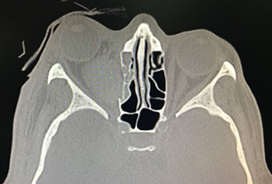

However, during the second postoperative day, and after performing a hemodialysis session, the patient presented increased edema, proptosis and hemorrhagic chemosis that exceeded the palpebral margin, limitation for ocular closure, right ophthalmoplegia and decreased vision. visual acuity to the point of not perceiving light, so he was assessed by the ophthalmology service who performed an emergency lateral canthotomy and a new CT scan of the orbits was requested, where a hematoma with dimensions of 1.9 x 2.1 x 3.0 cm, and an approximate volume of 6.2 cm3 (see Figures 2 and 3), persistence of sinking of the right lamina papyracea and no evidence of fracture of the maxillo-malar processes, or zygomatic arches, but a slight angulation was evidenced from the posterolateral wall of the right maxillary antrum; Considering a picture of retrobulbar hematoma in the right eye secondary to an open reduction of the floor of the orbit.

Figure 2 Right retrobulbar hematoma (black arrow). Taken from the radiological images of the patient.